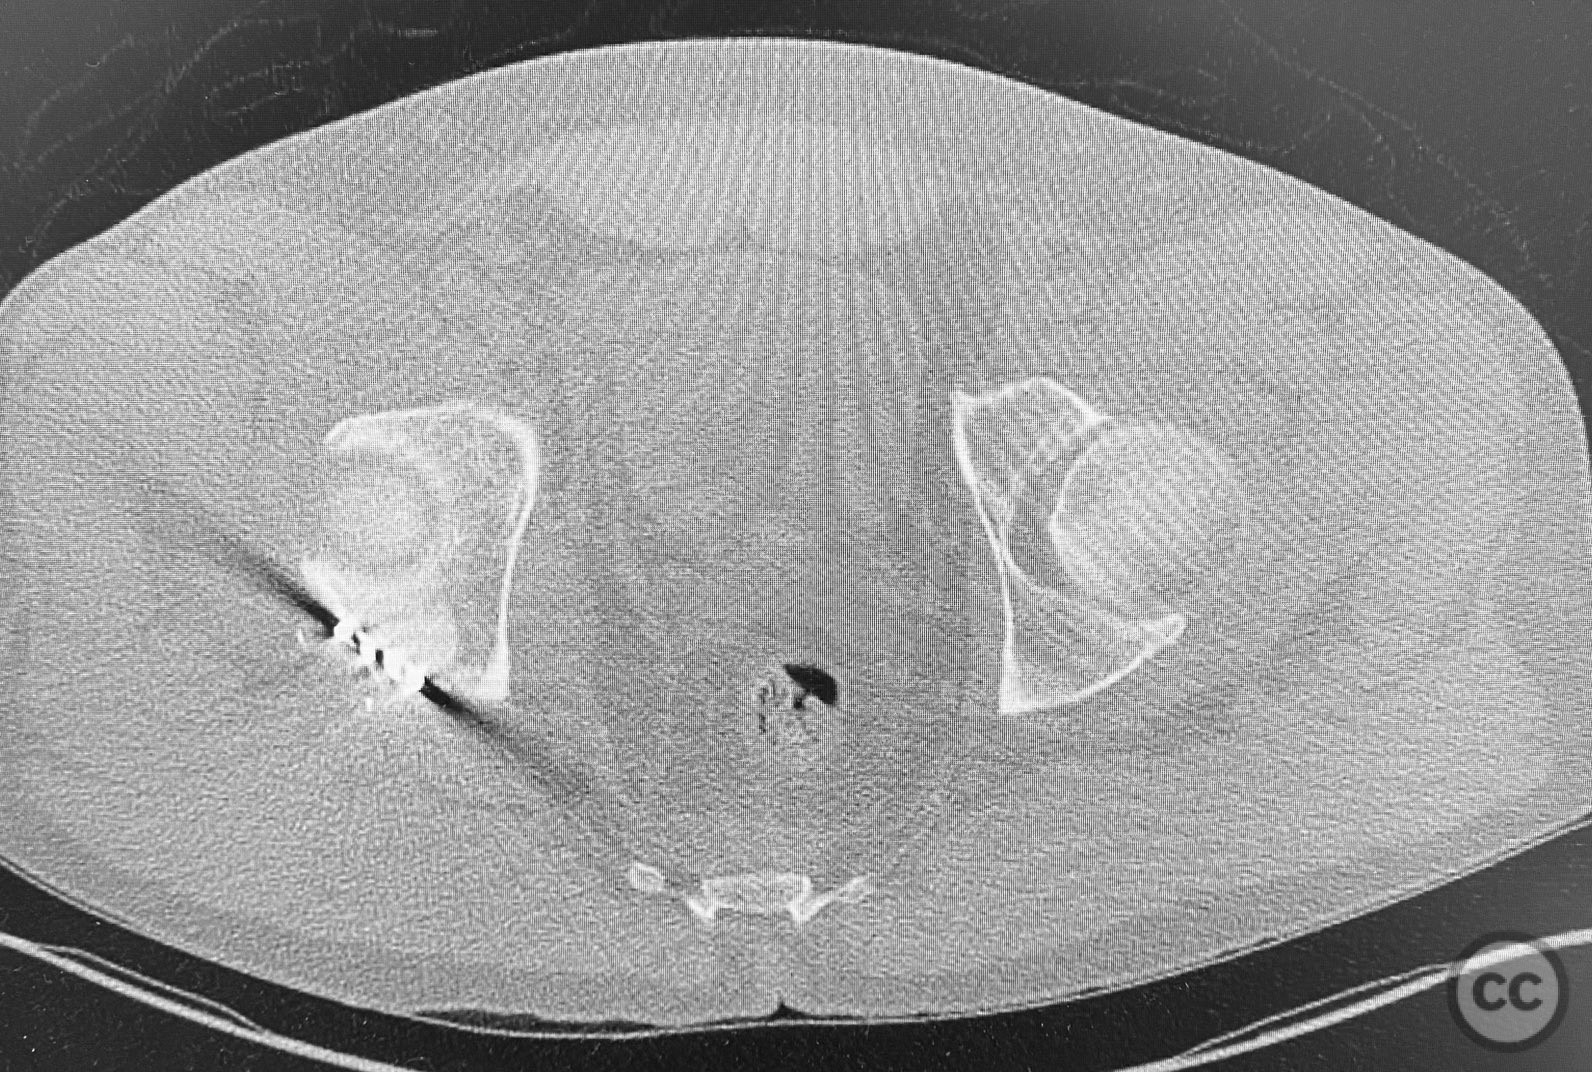

Clinical and radiological findings:  The patient sustained a comminuted acetabular fracture with multiple chondrocancellous articular fragments. The injury pattern is consistent with an AO/OTA 62-B3 (both column) acetabular fracture. Initial radiographs and computed tomography demonstrated displaced intra-articular fragments with associated segmental bone loss and wall involvement. No neurovascular compromise was documented.

Planning remarks:  The preoperative plan involved an extensile approach to the acetabulum, with the intention to carefully extract all chondrocancellous fragments for ex vivo cleansing, followed by dense packing of allograft bone grit into metaphyseal defects to support articular reconstruction. Sequential reduction of articular fragments was planned, followed by reduction and fixation of the acetabular wall using plate osteosynthesis.

All chondrocancellous fragments were meticulously removed from the wound and cleansed of hematoma and debris. Dense allograft bone grit was packed into metaphyseal defects to provide subchondral support. Each articular fragment was anatomically reduced and provisionally stabilized. The posterior wall was then reduced and definitive fixation achieved using contoured reconstruction plates. Attention was paid to restoring the congruity of the acetabular dome and maintaining anatomic reduction throughout the sequence.